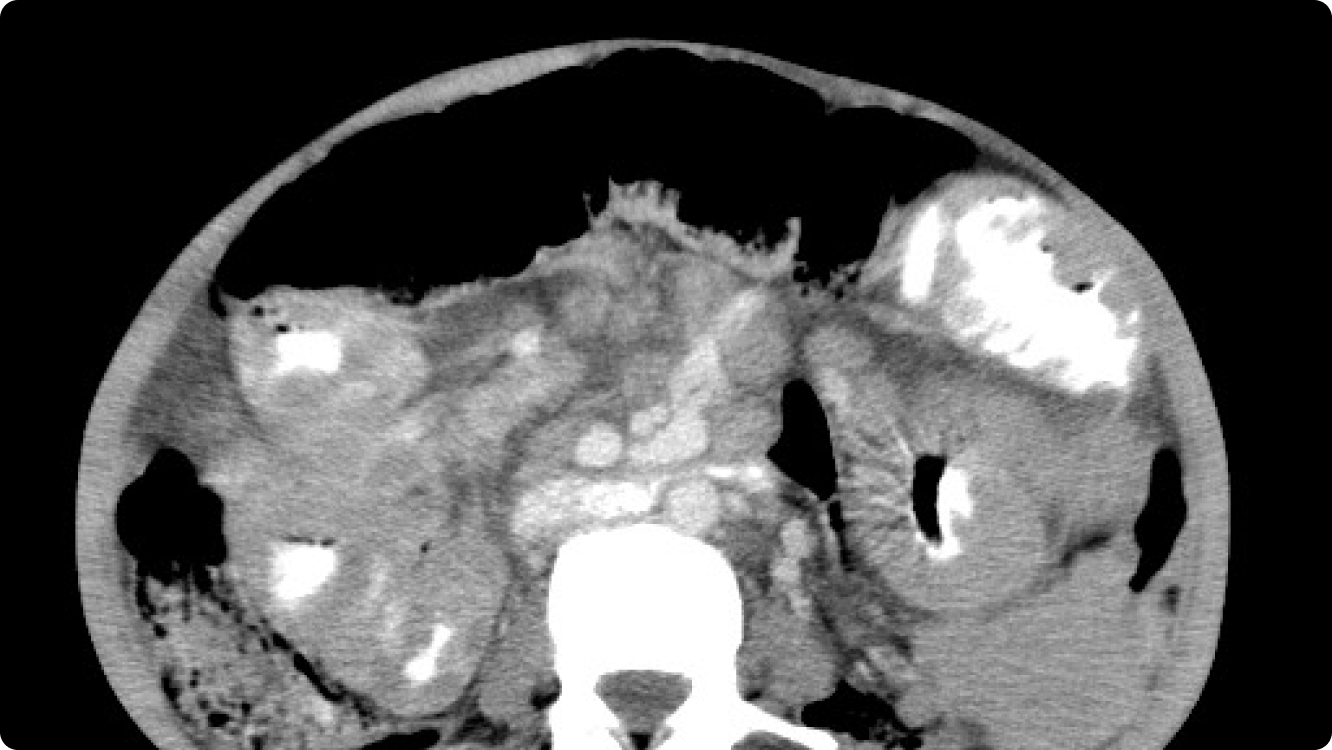

Continue readingCase 2- AIDS RELATED LYMPHOMA-CT OVERVIEW

NON HODGKIN>>> HODGKIN •ATYPICAL, MORE AGGRESSIVE, POOR PROGNOSIS •EXTRANODAL DISEASE MORE COMMON THAN SEEN IN NORMAL INDIVIDUALS •NOT RELATED TO CD4 COUNT BUT SEEN IN MID /LATE PHASE